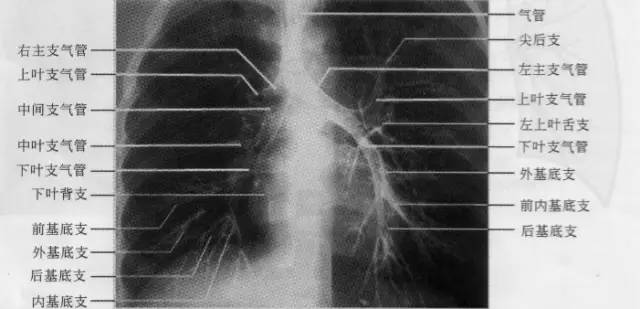

在高千伏或常规胸片上,气管和肺门区的主、叶支气管可以显示;肺段以下支气管因与周围含气肺组织缺乏对比,而不能显示。须借助于支气管造影方能显示其分布和腔内状况。

气管起自喉部环状软骨(12~19个,多为14~16个)下缘(相当于第6~7颈椎平面),长10~13cm(男子10.63cm,女子9.8cm),宽1.5~2.0cm(男子2cm,女子1.8cm),在第5~6胸椎平面分为左、右主支气管,其远端形成隆突角(或气管分叉角),正常该角为60°~85 °(女子略大于男子)。右侧主支气管粗短、陡直,平均长约2. 5cm,与体轴中线的夹角为20°~30°;左侧主支气管细长、倾斜,平均长约5cm(男子较女子稍长),与体轴中线的夹角为40°~55°。由于支气管的形态特点和右肺容积比左肺大,故气管内异物坠入有支气管的机会较多。两侧主支气管分别分出肺叶支气管,继而再分出肺段支气管,并继续逐级分支,直到终末细支气管。

右侧支气管分为上、中、下肺叶支气管及其所属10支肺段支气管。上叶支气管与右主支气管几呈直角向外侧分出,进入上叶后随即分出尖、后、前三支肺段支气管。自上叶开口向下至中叶开口的一段支气管是中间段支气管,无任何分支。自中间支气管下段前壁发出中叶支气管的内、外两支肺段支气管。下叶支气管为中间段支气管的直接延续.宽约1cm,主干甚短,共分为背支、内基底支、前基底支、外基底支和后基底支5支肺段支气管:在正位片上,四基底支自外向内的顺序,依次为前、外、后、内;侧位片上,自前向后依次为前、内、外、后。左侧支气管分为上、下肺叶支气管及其所属8支肺段支气管。左上叶尖后支相当于右上叶的尖支和后支;左下叶前内基底支相当于右下叶的前、内基底支;左侧无中间支气管,相当于右中叶的左上叶舌支直接开口于上叶支气管(如下图)。